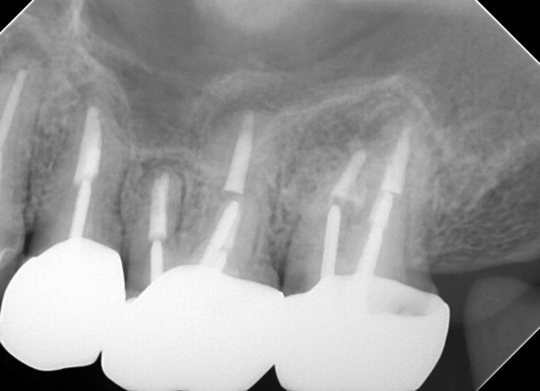

治療後

症状はすべて改善、経過3年後

根の周りが白っぽく骨ができています

骨の穴は完全に消えました